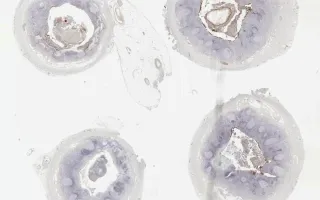

Adenovirus is a nonenveloped virus with a double stranded DNA genome that rarely infects the gastrointestinal tract. It has been described in association with mesenteric adenitis and ileocecal intussusception. In addition, it can induce a marked reactive lymphoid hyperplasia of the appendix that can mimic acute appendicitis clinically. In these cross-sections of the appendix, note the Cowdry type A eosinophilic nuclear inclusions in many of the enterocytes. Immunohistochemistry for adenovirus demonstrates strong nuclear staining within the mucosa.

This slide shows IHC stain. See related content for H&E stain.